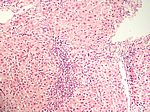

Aktive aggressive chronische Hepatitis, HE